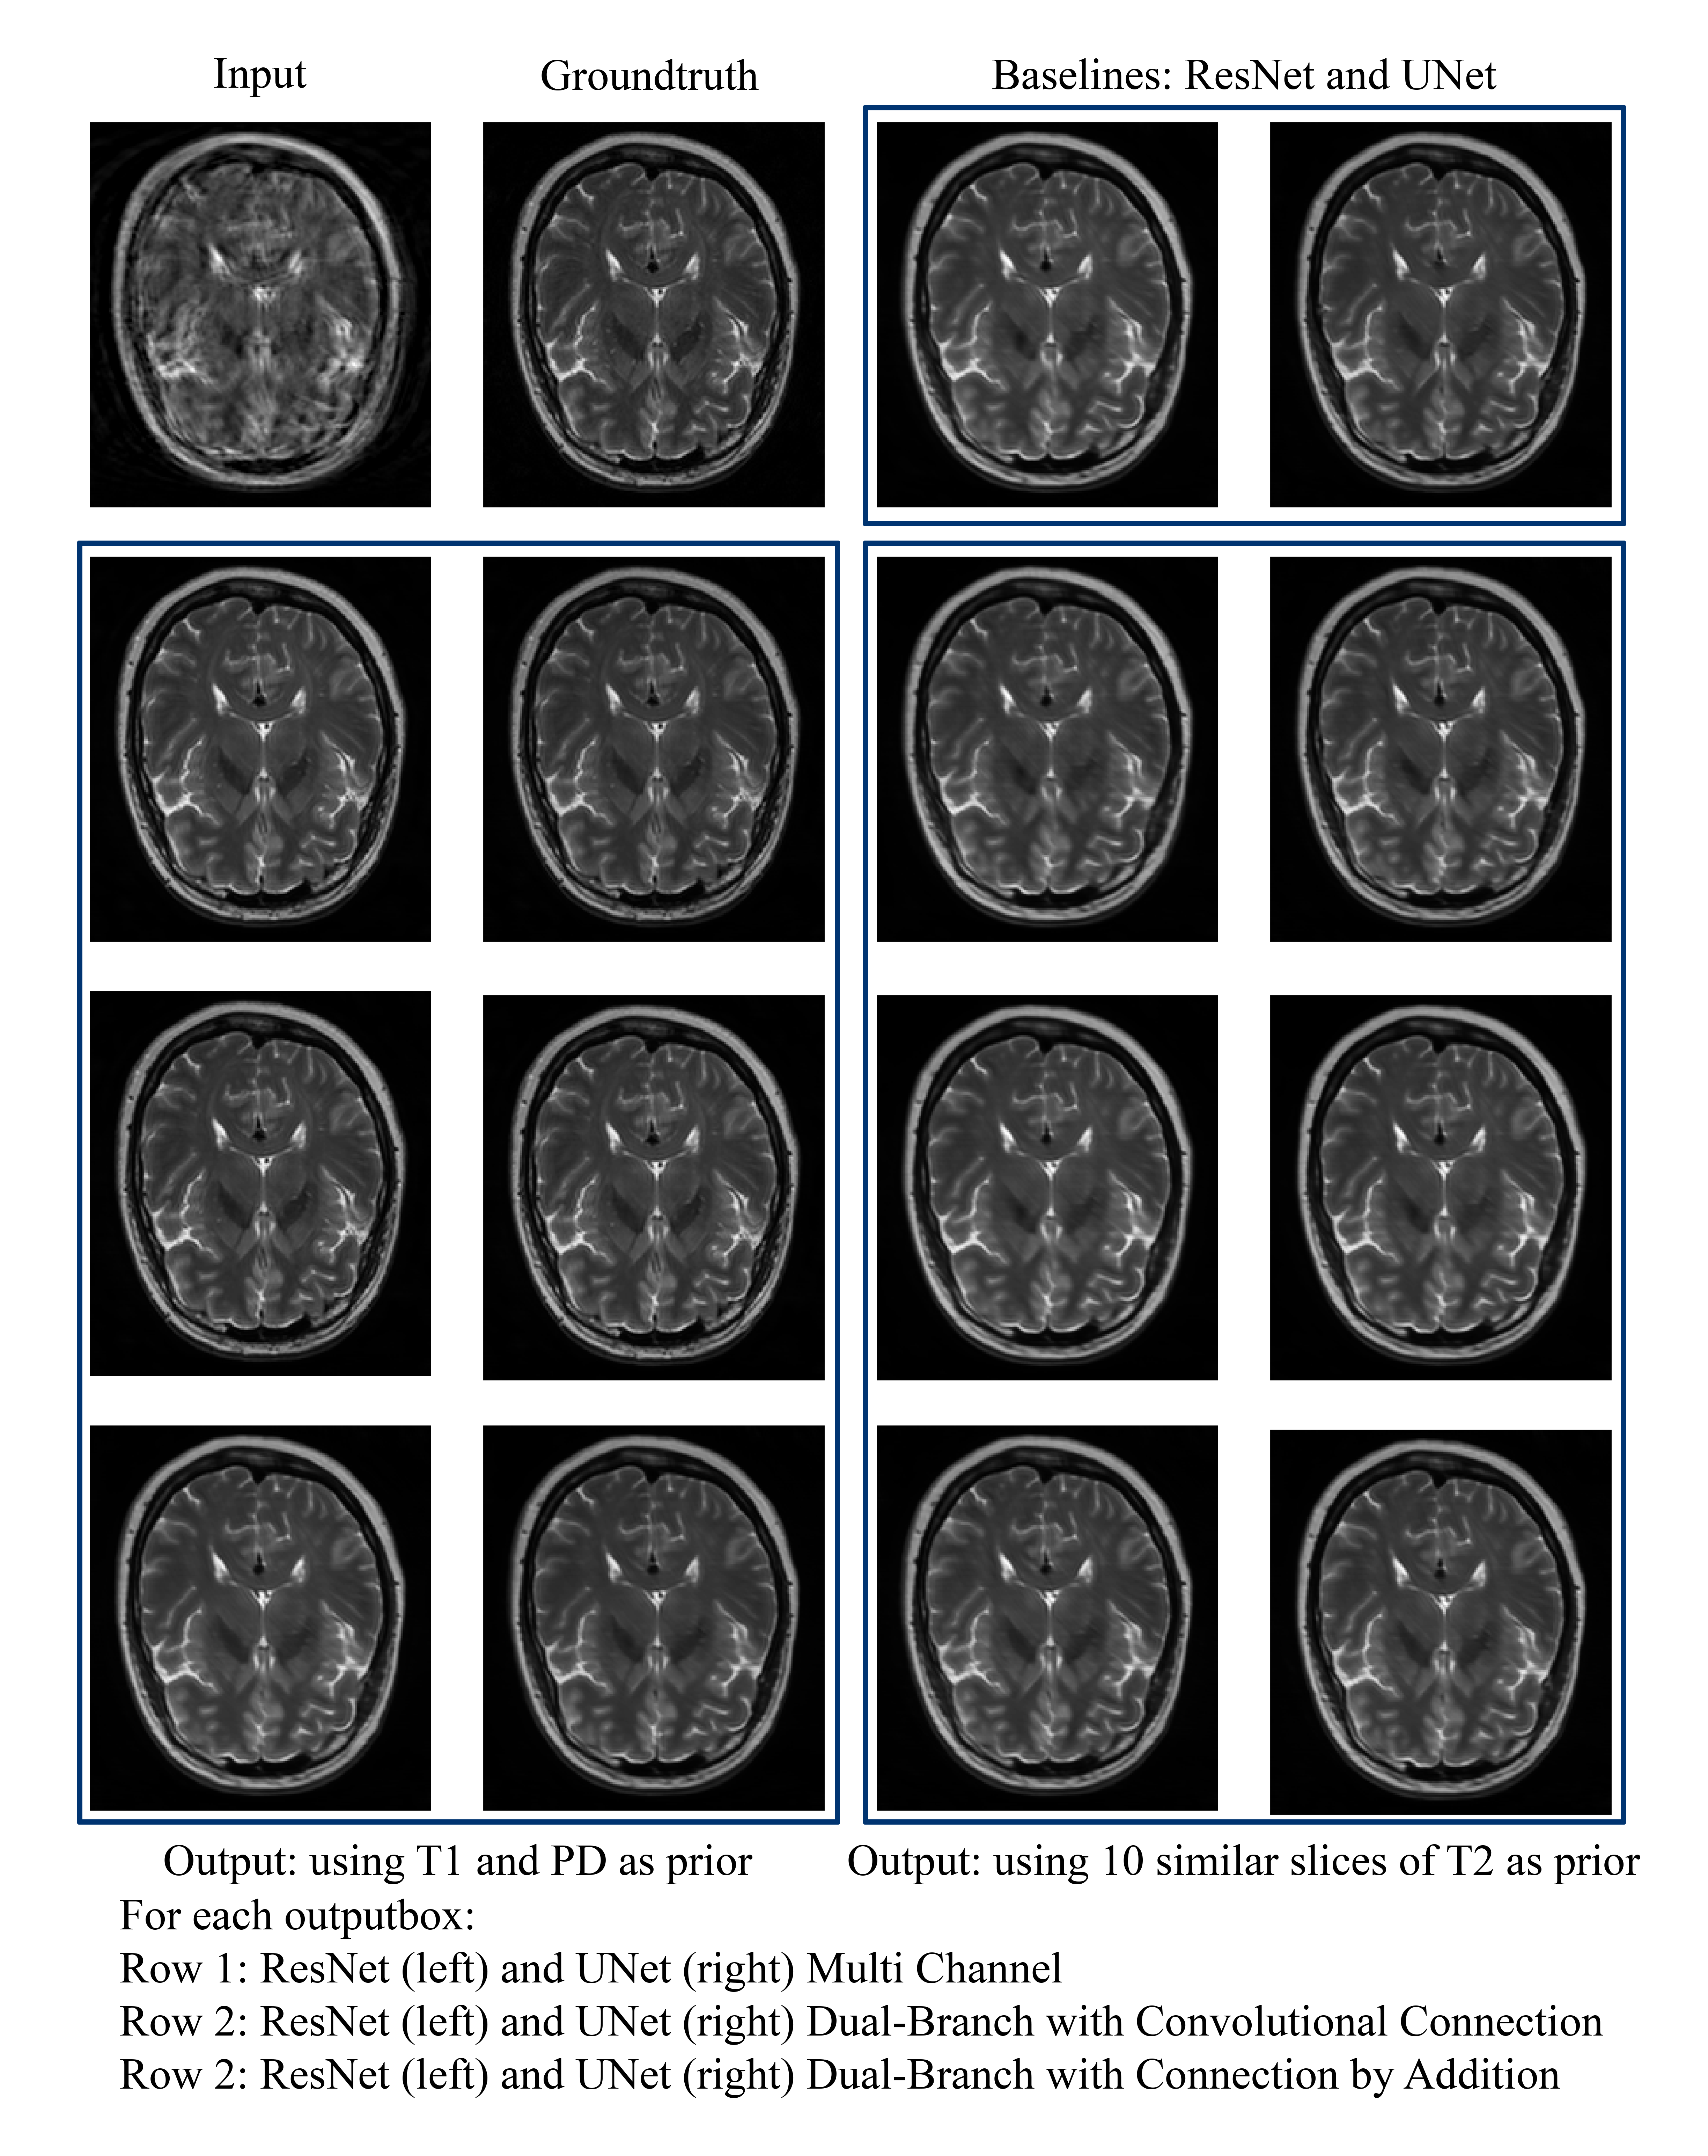

Figure 1 shows the performance of the different methods based on the SSIM [19] values and Figure 2 shows a representative example result. Between the two different types of priors, it was observed that supplying ten similar slices of the same contrast but of different subjects did not improve the motion correction. Nonetheless, supplying different contrasts of the same subject improved the motion correction significantly for most of the tests carried out. ResNet’s performance improved for both types of prior supply methods - multi-channel and dual-branch. For UNet however, only the multi-channel approach has shown significant improvement.

Figure 2: One example slice to show the motion correction performance of the various methods